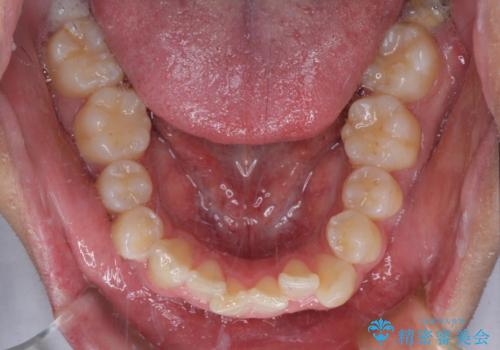

下顎前歯は後戻りを起こしやすいため、舌側を細いワイヤーで固定し、マウスピース型リテーナーで保定を行うこととしました。